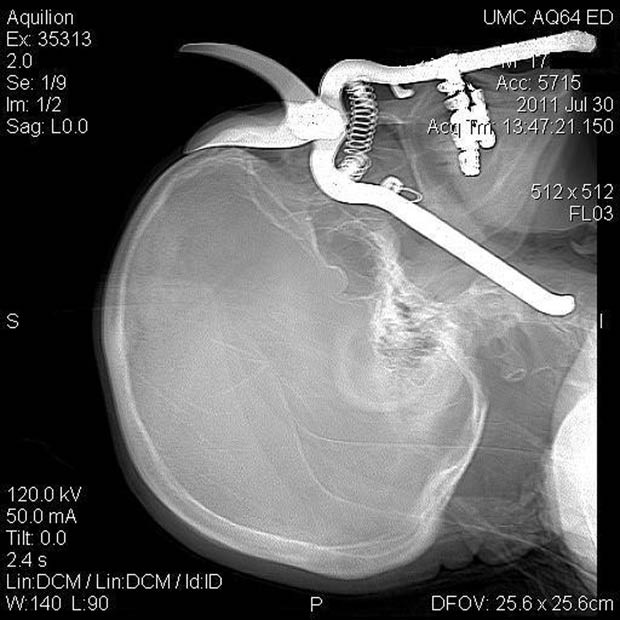

| Một ông lão 86 tuổi đã bị dụng cụ làm vườn đâm vào mắt khi bị ngã trong vườn. Tuy nhiên, ông có thể hồi phục sau tai nạn này |